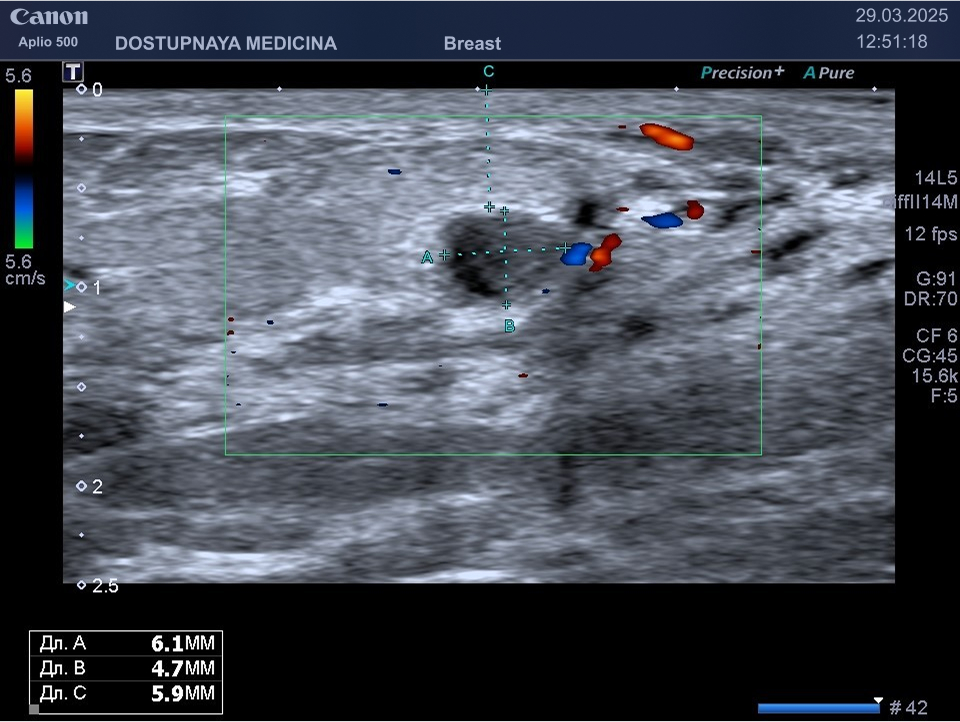

При ультразвуковом исследовании в кисте может быть визуализирован папиллярный компонент с кровотоком в режиме ЦДК. Так могут выглядеть цистаденопапилломы, которые считаются аблигатным предраком.